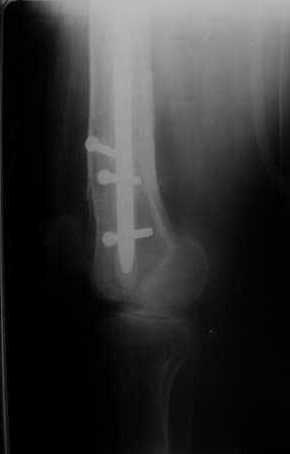

Мы демонтировали спице-стержневой аппарат, рассверлили костно-мозговой канал (до 14 мм), установили в канал спейсер с антибиотиком и произвели его блокирование четырьмя винтами ( рис. 1, 2, 3, 4).

В качестве армирующего элемента для спейсера мы использовали титановый неканюлированный штифт типа UFN (диаметр 9 мм, длина 400 мм). Проксимальную широкую часть штифта костным цементом не покрывали (рис. 5).

Дистальные блокирующие отверстия в цементе рассверлили после его застывания под ЭОП'ом. В проксимальном отломке использовали винт-полер (так как штифт проходил очень близко к переднему кортикальному слою).

Завтра пациент выписывается. Температура тела и анализы у него нормальные. Бедро мягкое, отечность тканей значительно уменьшилась. Послеоперационные раны зажили первичным натяжением. Укорочение конечности составляет 1,5 см (по ощущениям больного, это оптимальная длина ноги для него, так как у него анкилоз коленного сустава и голеностопного сустава в положении подошвенного сгибания). Пациент ходит с дозированной нагрузкой на конечность (10% от веса тела). Свищ на передне-наружной поверхности средней трети бедра, который открылся за неделю до последней операции рядом со стержнем аппарата, закрылся 5 дней назад (рис. 6,7, 8).